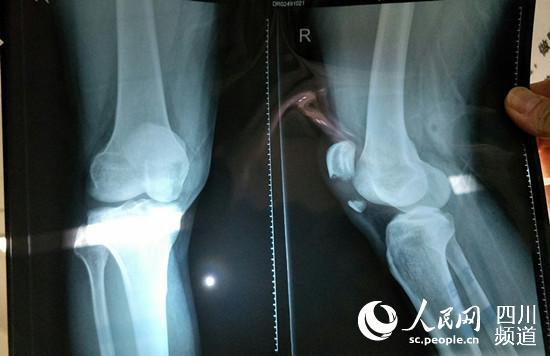

扒手拼命反抗追捕 致成都民警摔倒髕骨骨折(圖)

程皞的X光片。